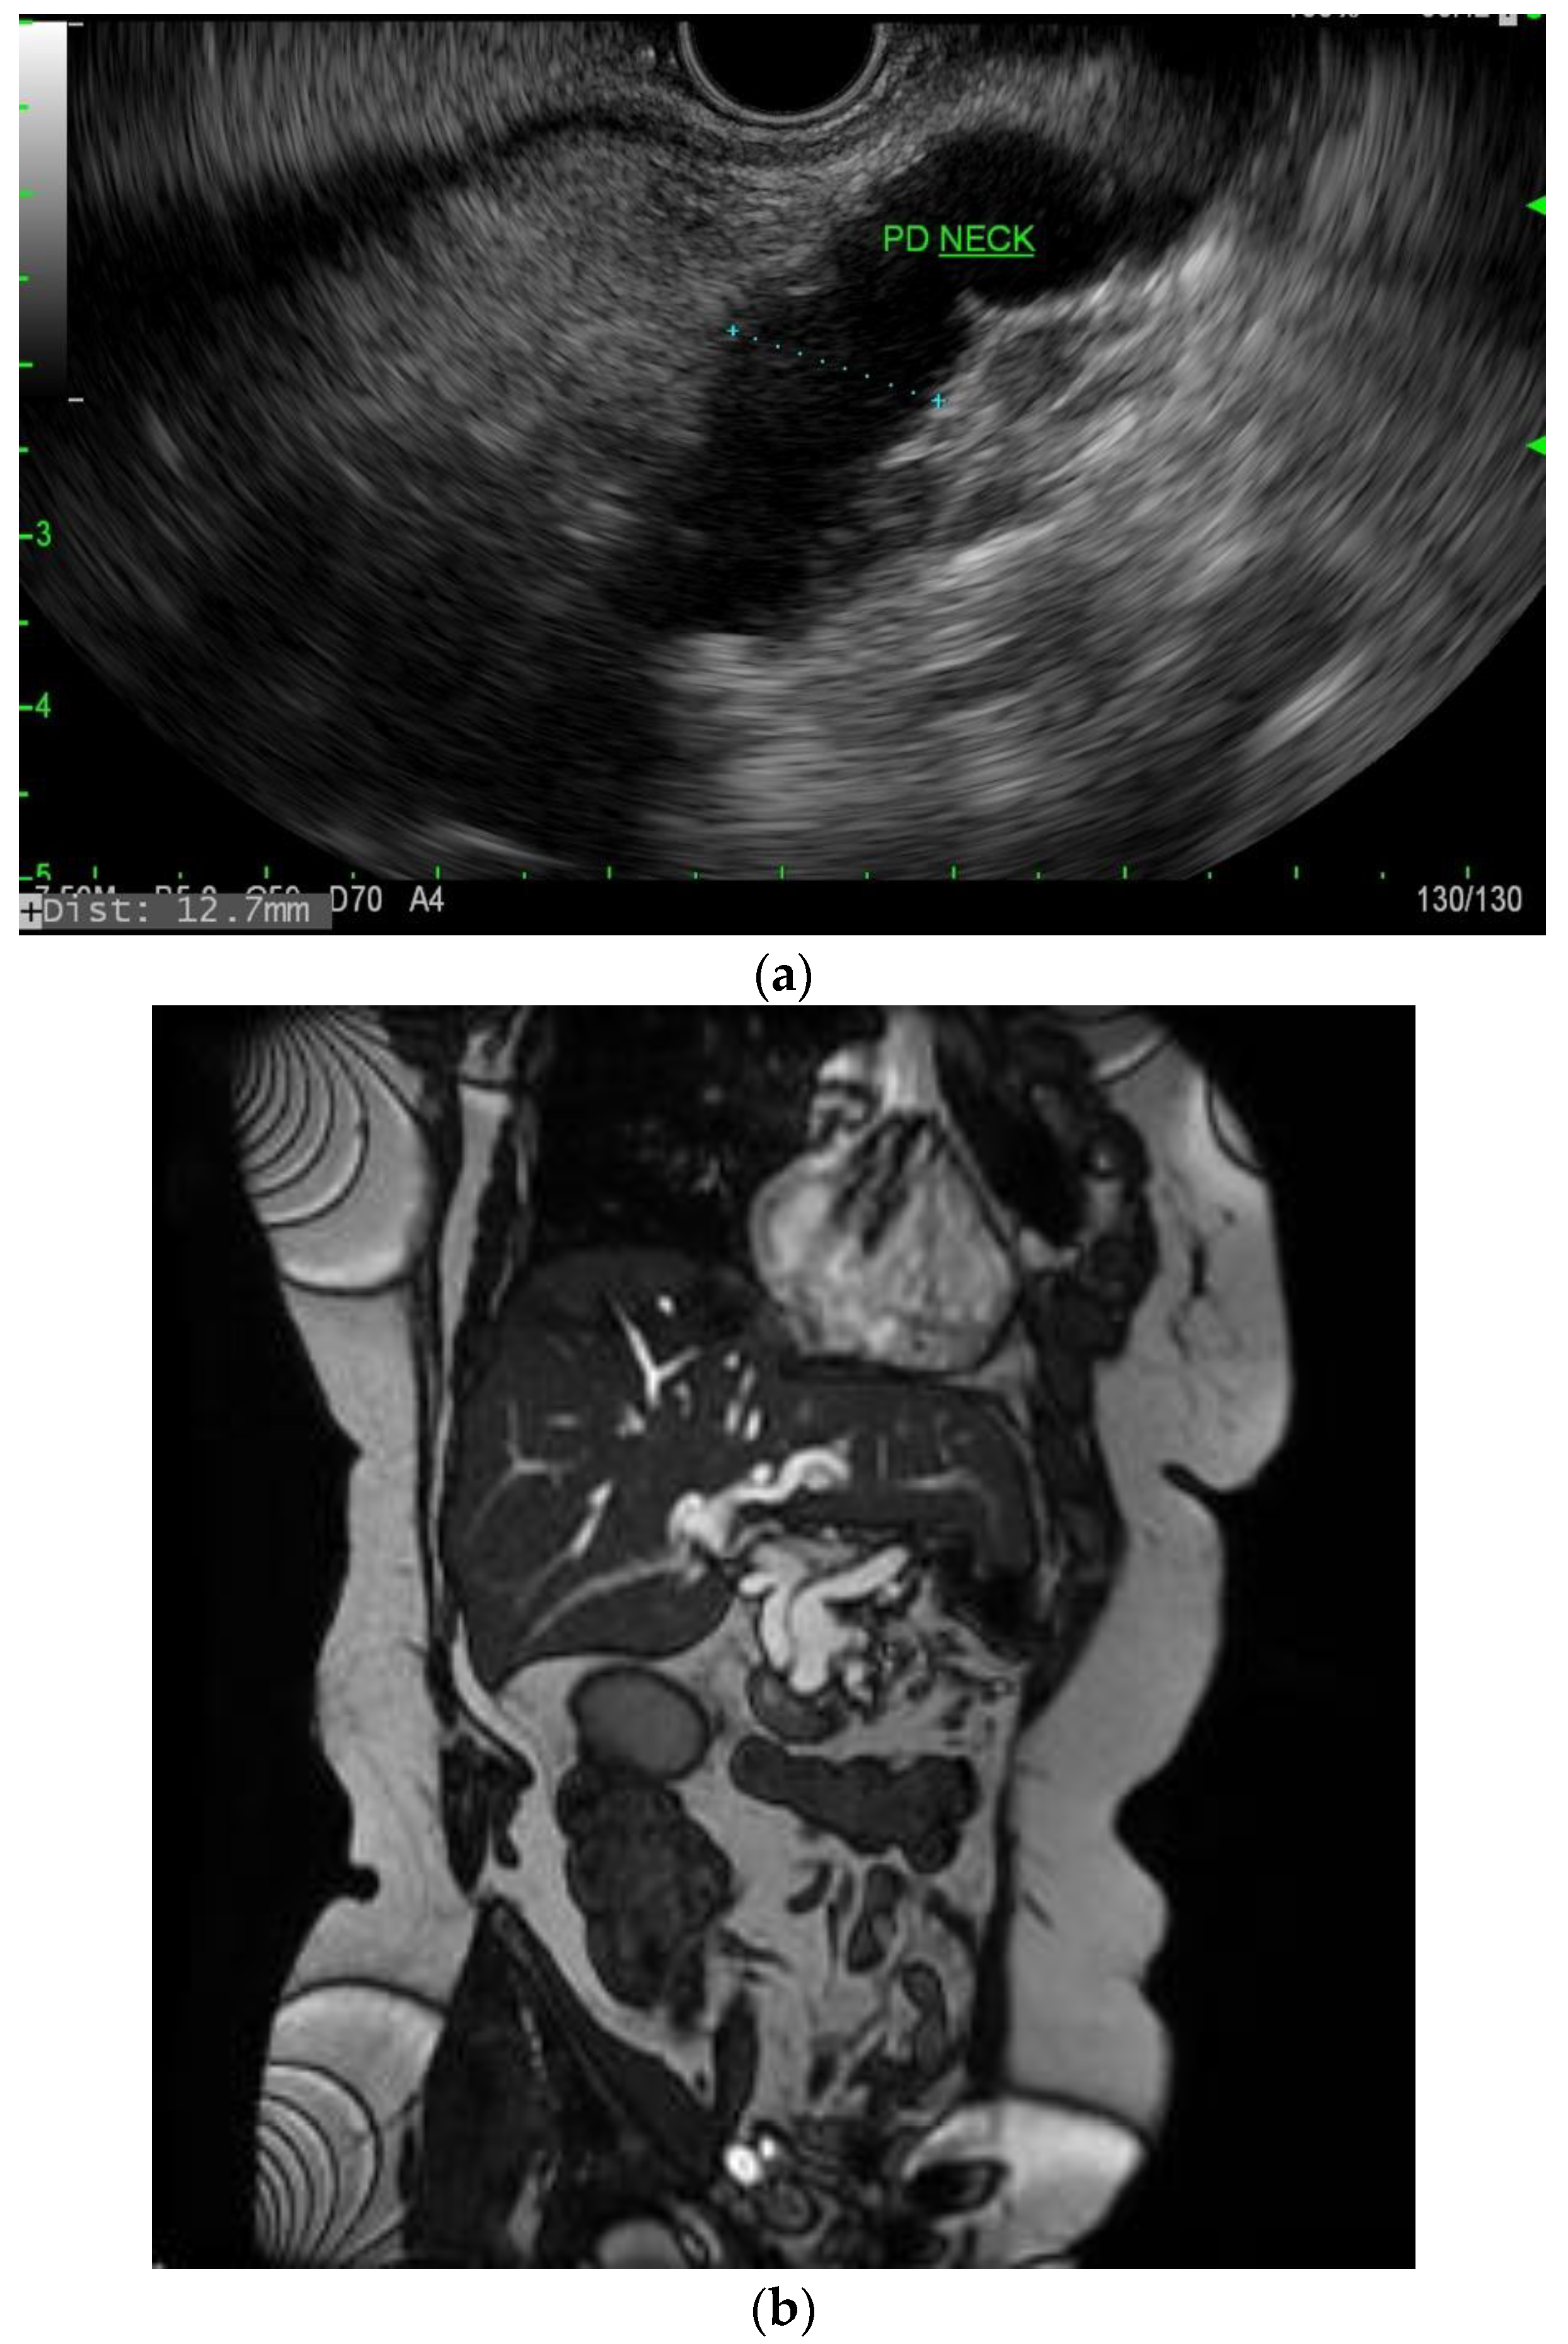

Figure 2.

(a) EUS image of main duct IPMN; (b) MRI image of main duct IPMN.

IPMNs can be divided into main duct intraductal papillary mucinous neoplasm and branch duct intraductal papillary mucinous neoplasms, with dilation of the main pancreatic duct helping to distinguish between the two. They usually present in the fifth to seventh decade of life and have an equal distribution between males and females [15]. Intraductal neoplasms are typically associated with a dilated main pancreatic duct (Figure 2a,b), whereas the branch duct IPMNs are associated with a dilated pancreatic duct branch or branches (Figure 3). A mixed IPMN is defined as a cystic lesion with ductal communication and main pancreatic duct dilation greater than or equal to 5 mm (Figure 4). Diabetes mellitus (DM) and a family history of pancreatic adenocarcinoma are known risk factors for IPMN, with odds ratios of 1.79 (CI 95%: 1.08–2.98) and 2.94 (CI 95%: 1.17–7.39), respectively [16]. Cytology can show columnar cells with variable atypia and can stain positive for mucin. CEA is usually greater than 200 ng/mL in approximately 75% of lesions, similar to mucinous neoplasms. Main duct IPMNs have a 36–100% risk of malignant potential, compared to a lower risk of 11–30% malignant potential of side branch IPMNs [17].